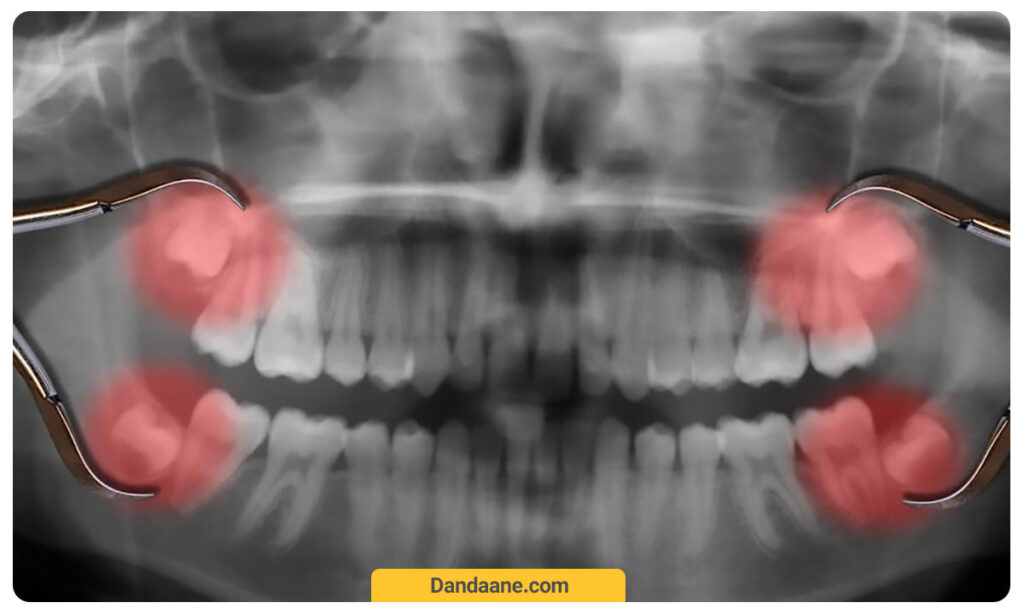

دندان نهفته به دندانی گفته می شود که نتوانسته باشد از لثه خارج شود و زیر لثه باقی مانده باشد. علت نهفته شدن دندان ها در اکثر مواقع عدم وجود فضای کافی در فک برای رشد و همچنین نیفتادن به موقع دندان شیری یا مسدود شدن راه خروج دندان دائمی است.

دندان عقل که معمولاً آخرین دندانی است که از لثه بیرون میزند بیشتر دچار نهفتگی می شود. این دندان ها به طور معمول در سنین 17 تا 21 سالگی از لثه بیرون می زنند. بنابراین بیشتر اوقات اگر حرفی از دندان نهفته شد منظور دندان عقل است. هرچند که دندان های دیگر نیز ممکن است دچار نهفتگی شوند.

با رویش دندان عقل (که به آن “دندانهای آسیاب سوم” نیز گفته می شود) رشد فک اغلب متوقف شده است. بنابراین دهان و فک برای جا دادن به آنها خیلی کوچک است. از آنجا که در این شرایط دیگر واقعاً نیازی به دندان عقل نیست، اگر مشکلی ایجاد شود معمولاً اقدام به کشیدن دندان می کنند. اگر شما فک کوچکی دارید، احتمالاً دندان عقل نهفته دارید.